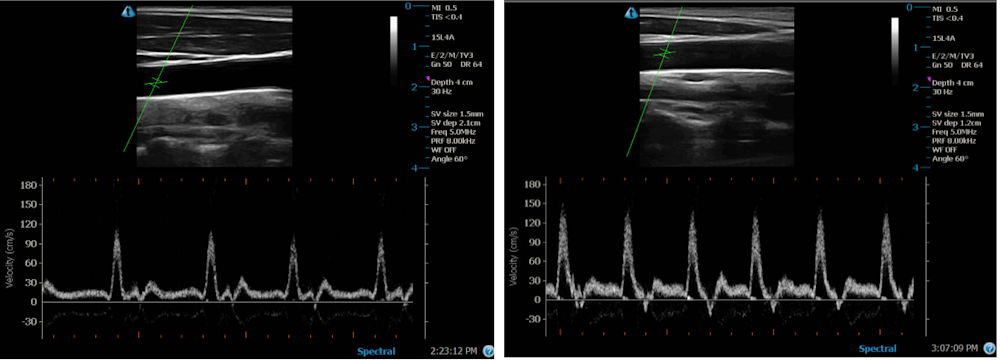

Погружение в ванну или пребывание в сауне приводит к «пассивному нагреву» тела, который начинается с приятного ощущения тепла, а затем вызывает ощущение жара и провоцирует обильное потоотделение, сопровождаемое незначительным учащением пульса. Ультразвуковое сканирование артерий добровольцев, проведенное в ванне и сауне, показало, что от прогрева у них усилился кровоток. Те же самые реакции организм выдает и во время физической активности, хотя она, безусловно, куда более эффективно сжигает энергию.